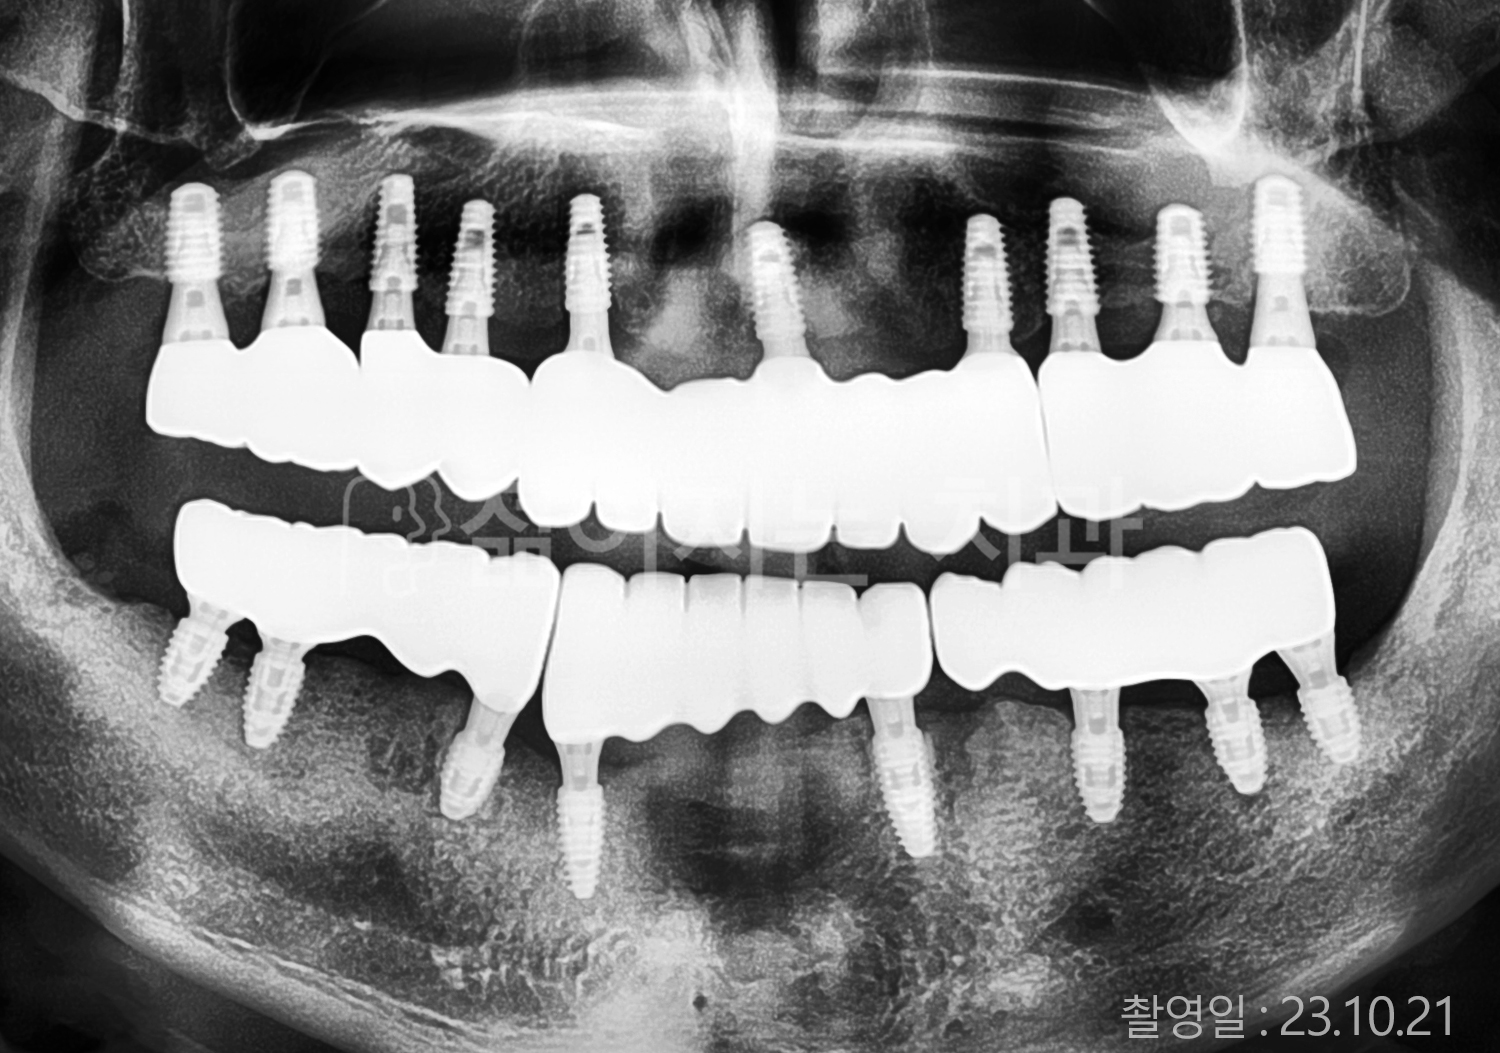

• 70대 고혈압, 고지혈증 전체치아 10개 이상 임플란트

• 60대 당뇨, 간염 전체치아 10개 이상 임플란트

• 80대 골다골증 전체치아 6개 이상 임플란트

• 70대 고혈압, 당뇨 전체치아 10개 이상 임플란트

• 60대 간 질환 전체치아 10개 이상 임플란트

• 60대 전체치아 10개 이상 임플란트

• 70대 전체치아 10개 이상 임플란트

• 50대 전체치아 10개 이상 임플란트

• 60대 고혈압, 고지혈증 전체치아 10개 이상 임플란트

• 40대 고지혈증, 뇌혈관 질환 전체치아 10개 이상 임플란트